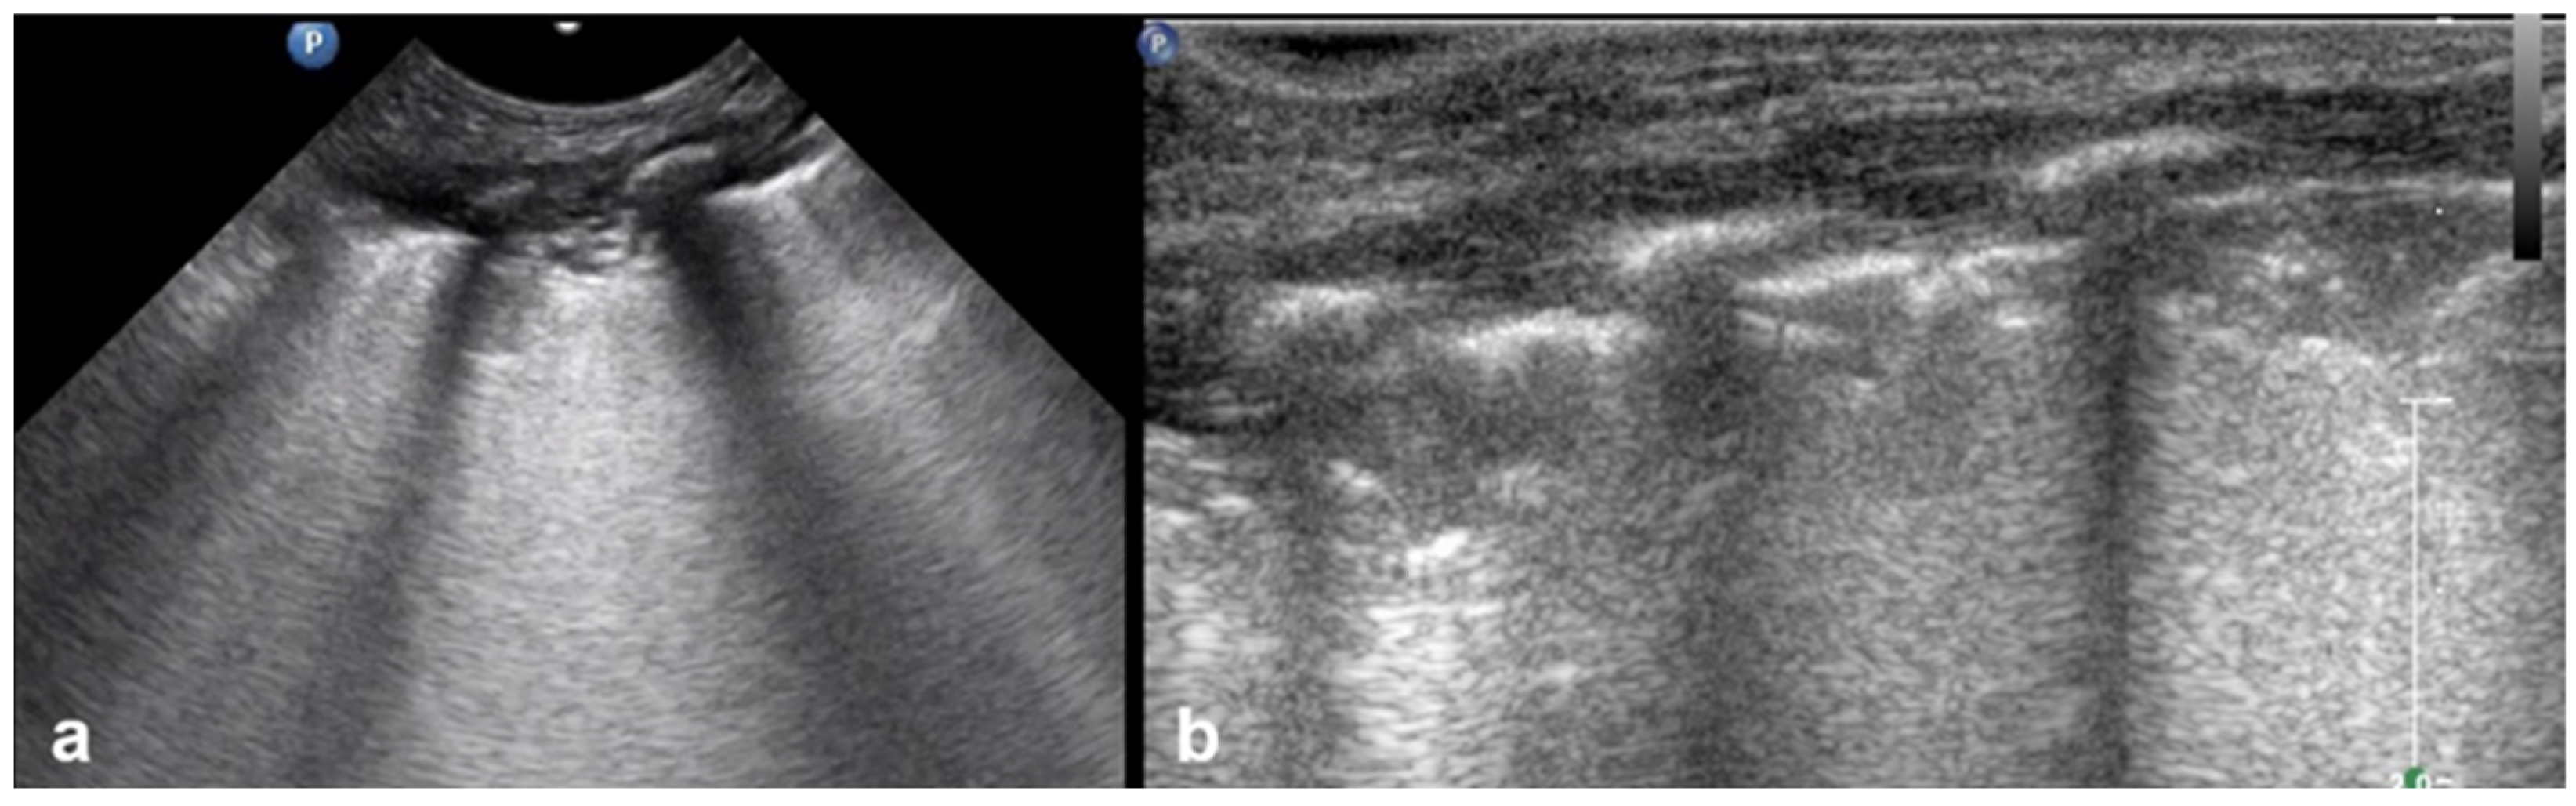

3.1.5. Sea-Shore Sign

3.1.6. Sinusoid Sign